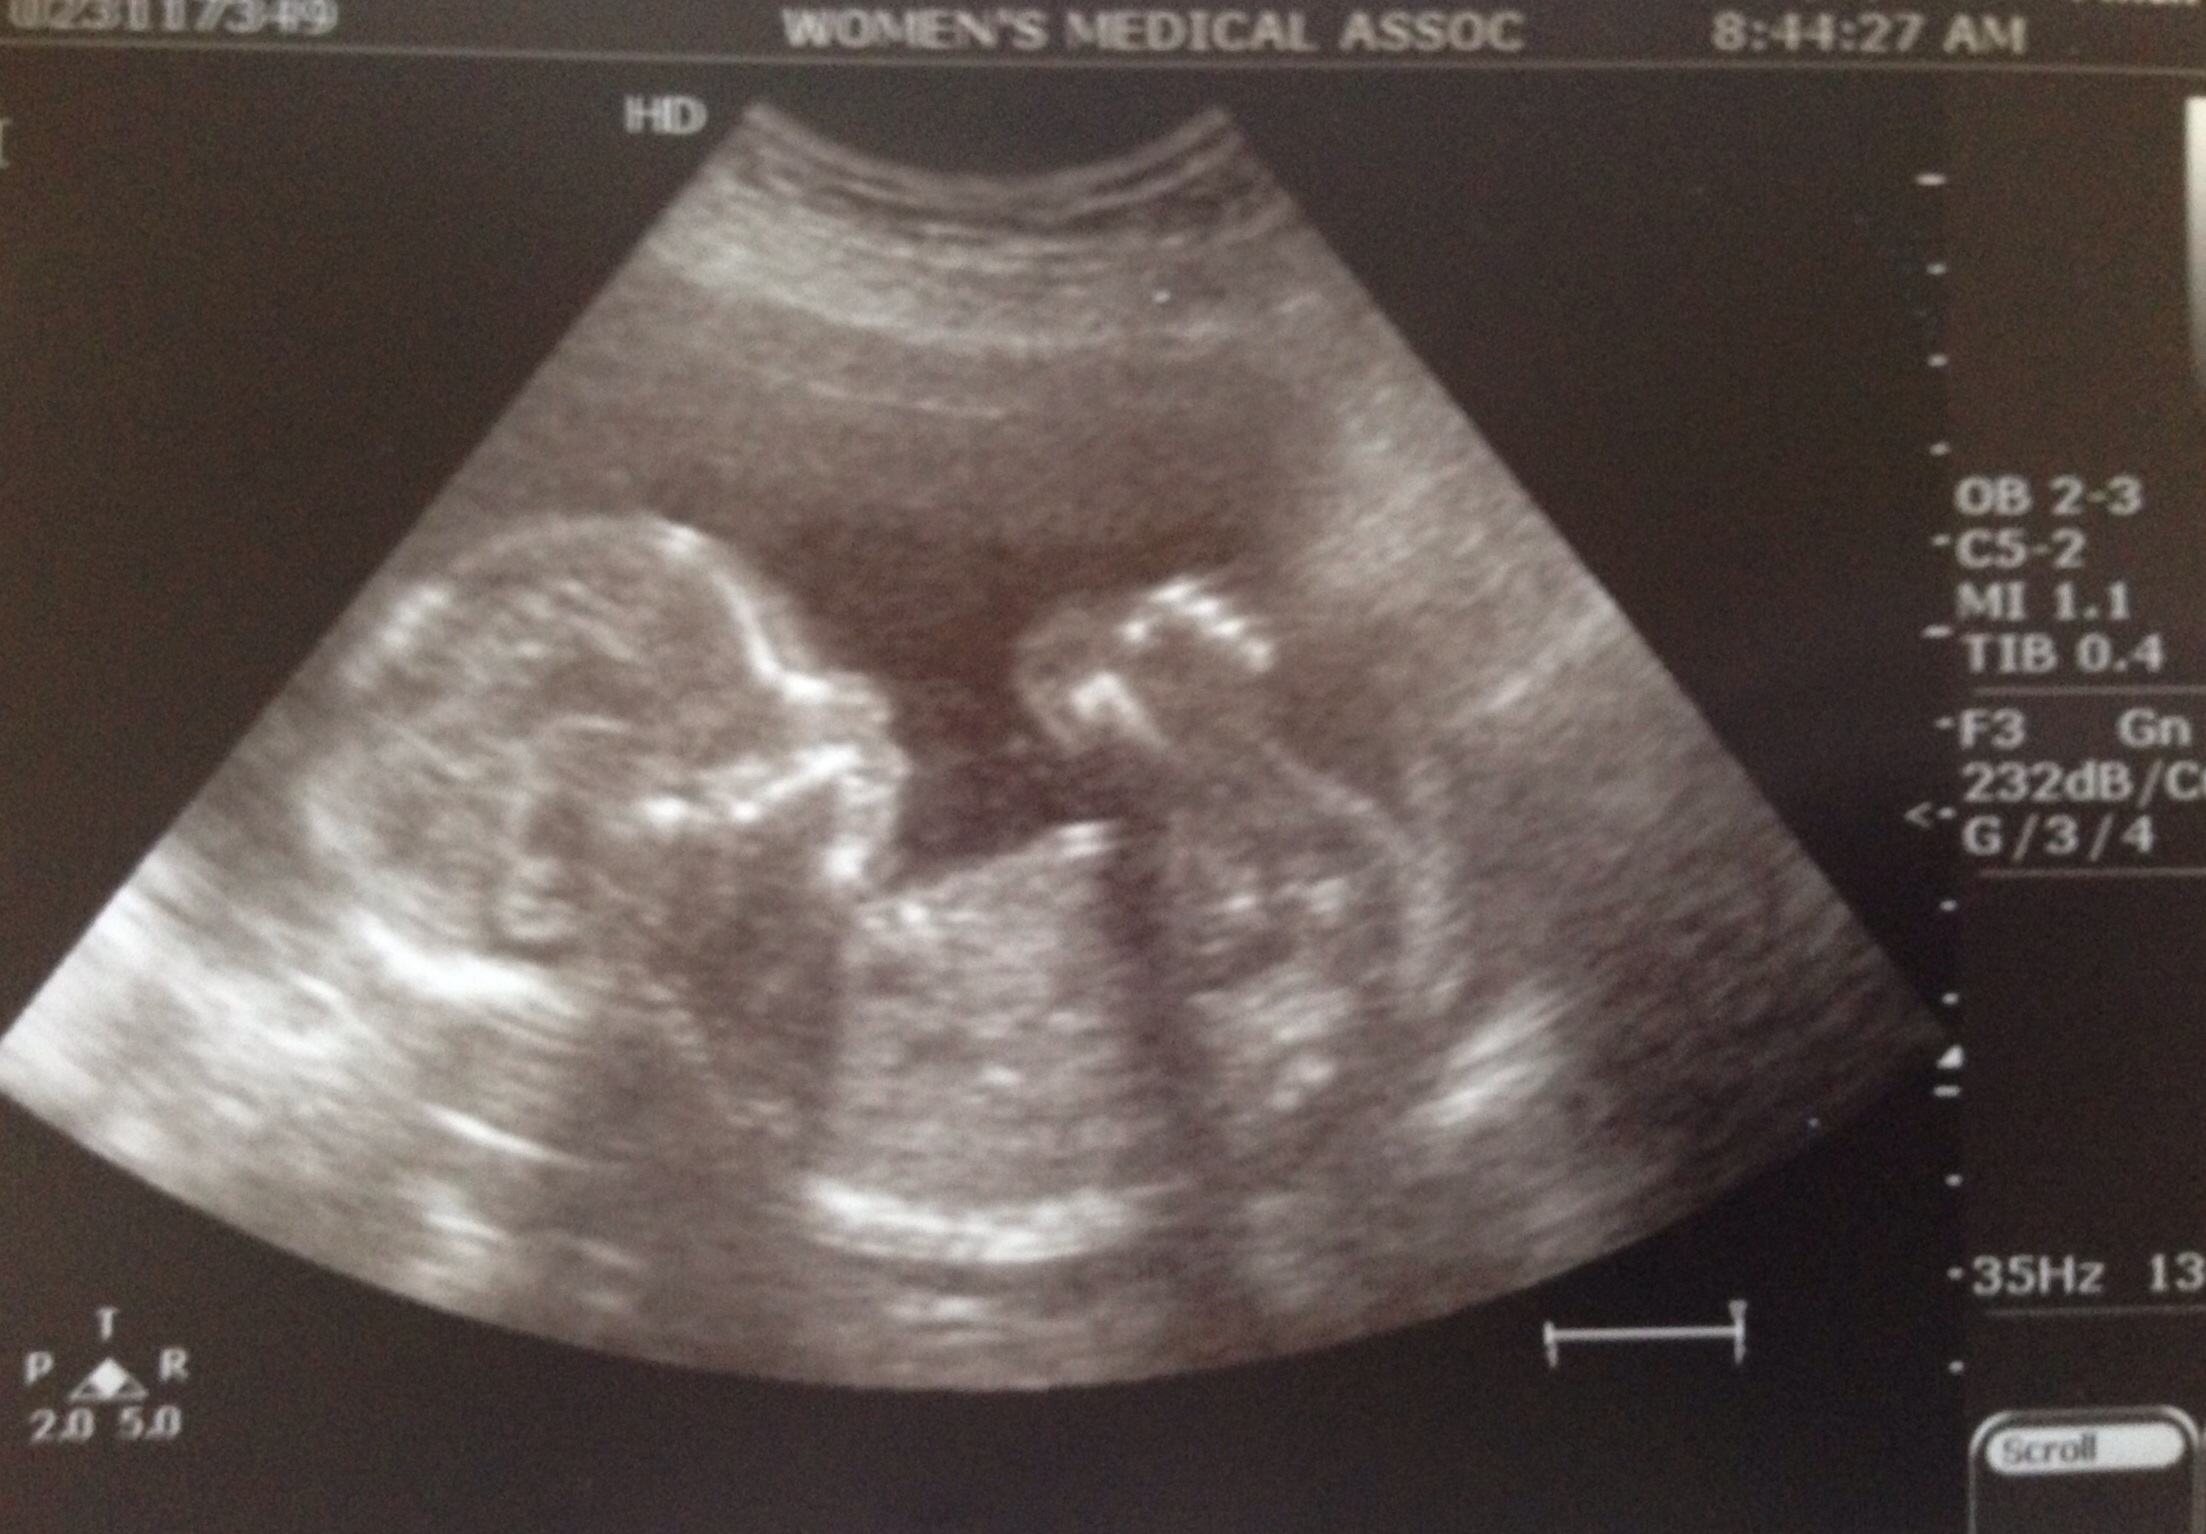

GIRL! (Or a seal, says my son) After 10 long years of IF, I finally have a boy and a girl! Woo hoo! She had her little arm between her legs. It took the tech about 15 minutes to get a clear shot. The suspense was crazy! The look on DS face when he heard girl was priceless. He said "mom, I'm gonna take really good care of her and protect her really well." We Can't wait to meet our little Harper Charlotte!